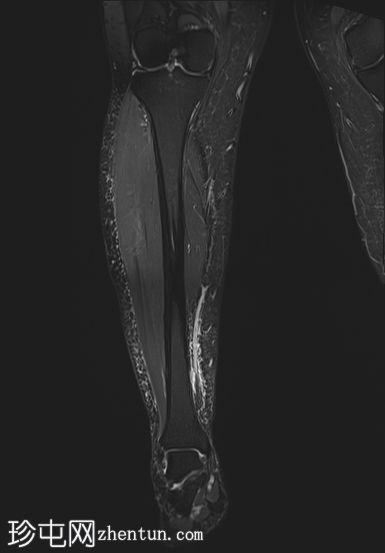

冠状位

STIR序列

2.jpg

PD/STIR序列显示肌腱交界处附近前侧肌纤维局灶性异常高信号,符合部分肌腱拉伤/撕裂。腓肠肌内侧头与下方比目鱼肌之间可见一条细小的液性裂隙,向上延伸——典型的网球腿表现。邻近肌间筋膜间隙轻度水肿。未见全层肌肉撕裂或肌腱回缩。未见血肿或积液。腓肠肌外侧头、比目鱼肌及其余小腿肌肉信号和体积均正常。所见骨骼未见异常。

网球腿通常累及腓肠肌内侧头的肌腱交界处,在STIR/PD像上表现为局灶性高信号,腓肠肌和比目鱼肌之间可见液性裂隙。

MRI可鉴别部分撕裂(保守治疗)与全层撕裂或大血肿(可能需要手术治疗)。

对于小腿疼痛,应始终将深静脉血栓形成(DVT)纳入鉴别诊断;如果临床怀疑DVT,影像学检查和临床表现相结合至关重要。